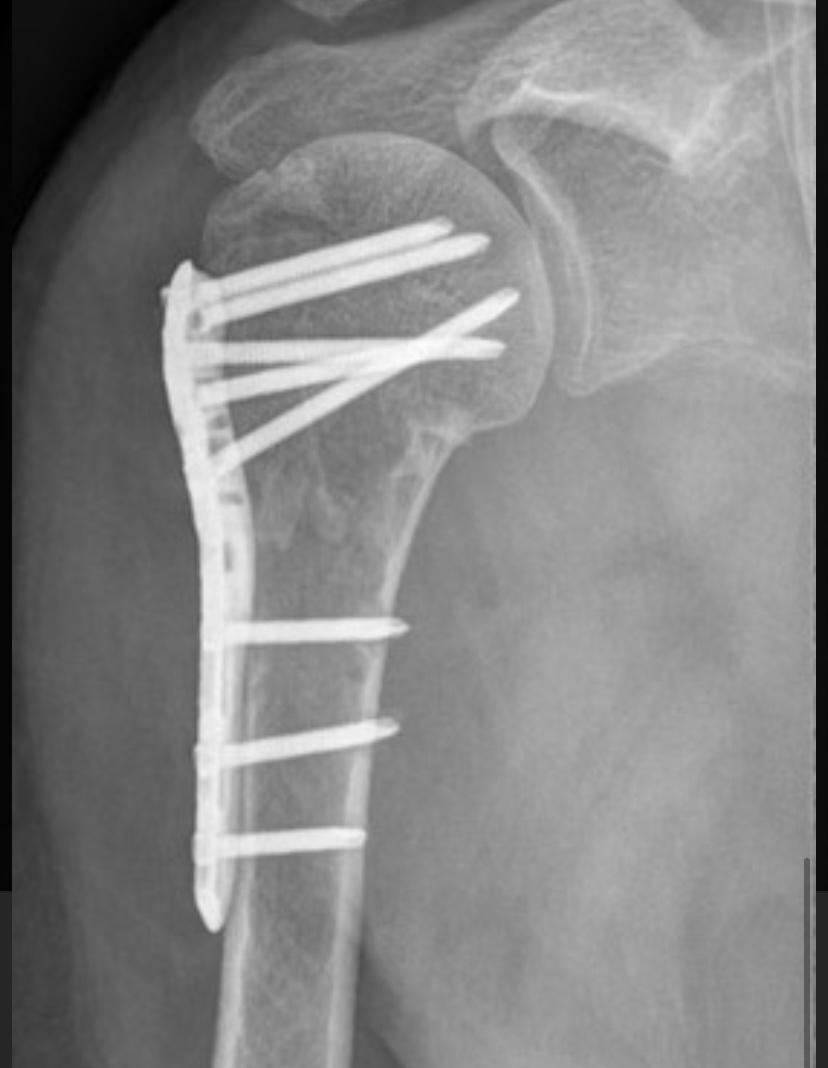

FRATURAS DO OMBRO

As fraturas do úmero proximal acontecem basicamente em 2 perfis de paciente: em jovens após acidente de alta energia, principalmente queda de moto, e outra, no paciente acima de 50 anos, que simplesmente caem, frequentemente relacionada ao osso com osteoporose. Dor no ombro, impossibilidade de mexer e hematoma. Este último pode se espalhar pelo peito e braço Após a avaliação médica, no serviço de emergência, exame de raio-X será solicitado. Algumas vezes a tomografia computadorizada esclarece detalhes quando a fratura é complexa. Ressonância magnética é solicitada nos casos em que a suspeita de fratura é grande, porém o exame radiológico é normal. São os casos de fraturas ocultas. O tratamento para a maior parte dessas fraturas é com tipóia. Repouso do membro acometido por aproximadamente 45 dias é suficiente para a consolidação do osso. A cirurgia é realizada para aqueles pacientes que apresentam grande desalinhamento dos fragmentos da fratura, fraturas dentro da articulação e fraturas com luxações. O principal meio de fixação é com placa e parafusos. Algumas vezes, dependendo do tipo de fratura e idade do paciente, é necessário substituir a região fraturada por uma prótese.